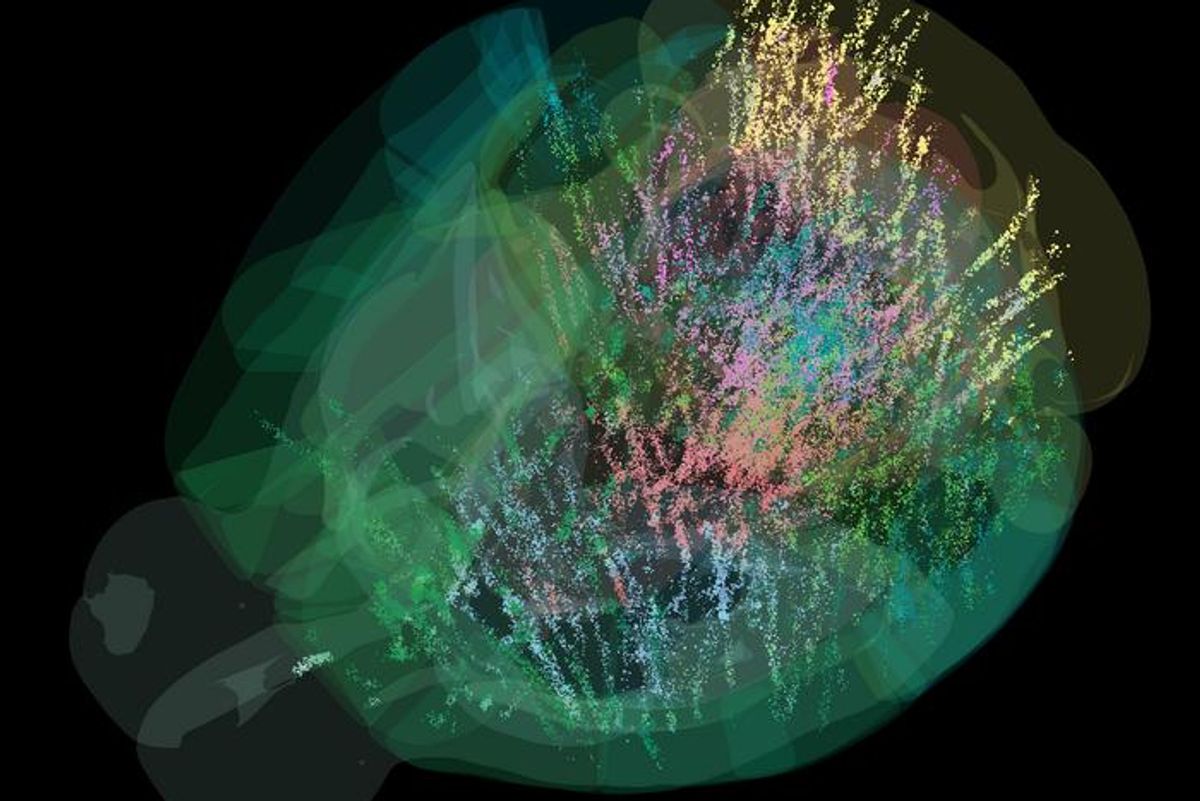

A Complete Brain Activity Map Now Exists, Giving us Insight to How We Make Decisions

Learn more about how researchers were able to fully map a mouse brain and give us a better understanding of how or why we make the decisions we do.